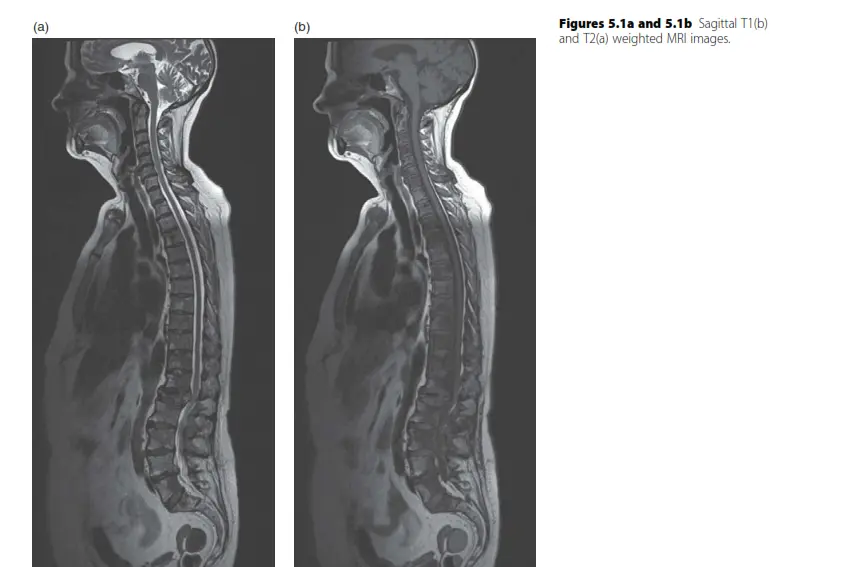

أورام العمود الفقري هي نمو غير طبيعي للخلايا داخل العمود الفقري أو حوله، قد تكون حميدة أو خبيثة. يتضمن علاجها التشخيص الدقيق عبر الرنين المغناطيسي والخزعة، ثم الجراحة، العلاج الإشعاعي، أو الكيميائي، بهدف تخفيف الأعراض والحفاظ على الوظيفة العصبية.

يعد العمود الفقري محور الجسم ومركز الجهاز العصبي، وحين يصيبه ورم، سواء كان حميداً أو خبيثاً، فإن ذلك يثير الكثير من القلق والخوف. أورام العمود الفقري هي نمو غير طبيعي للخلايا يمكن أن يتطور داخل العمود الفقري نفسه (العظام، الأقراص، الأربطة) أو داخل الحبل الشوكي أو حوله. يمكن أن تكون هذه الأورام أولية (تنشأ في العمود الفقري) أو ثانوية (نقائل من سرطان آخر في الجسم).

لفهم أورام العمود الفقري، من الضروري أولاً استيعاب التركيب التشريحي المعقد لهذه المنطقة الحيوية. يتكون العمود الفقري من سلسلة من العظام تسمى الفقرات (33 فقرة)، والتي تحيط وتحمي الحبل الشوكي الحساس. يمتد الحبل الشوكي من الدماغ إلى أسفل الظهر، وهو مسؤول عن نقل الإشارات العصبية بين الدماغ وبقية الجسم، ممرراً الأوامر الحركية من الدماغ إلى العضلات والإشارات الحسية من الجسم إلى الدماغ.